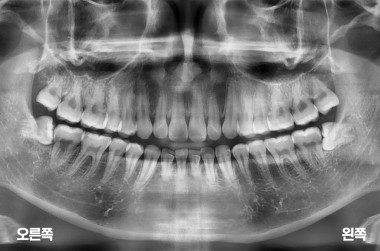

3

사랑니 3개 발치